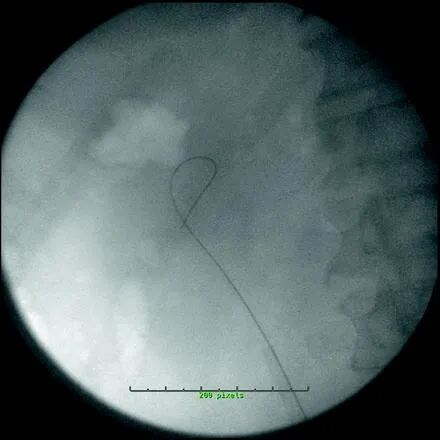

技术:肾结石

在我们的机构,我们经常使用 UAS 来治疗肾结石。术前未置入支架的患者,选用12/14 F UAS,术前置入支架的患者,尤其是结石负荷较大的患者,选用14/16 F UAS。对于女性,选择 35 厘米的长度,除非她们的身高低于 152 厘米,在这种情况下,使用 28 厘米的护套。对于男性,选择 45 厘米长的 UAS(表 24.2)。该过程首先通过使用膀胱软镜将亲水性尖端线向上穿过输尿管来启动。应拍摄并保存肾脏的图像以供参考。用直导管排空膀胱。如果怀疑合并输尿管结石,则使用 8-10 同轴扩张器扩张远端输尿管,并使用低于 7.0 F 的半刚性输尿管镜检查输尿管。如果怀疑没有输尿管结石,则通过 5 F 开口导管进行逆行肾盂造影。逆行肾盂造影可将结石证明为充盈缺损,识别其他病理,重要的是,它将描绘出上输尿管和 UPJ 的解剖结构,这将指导 UAS 的放置 8-10 同轴扩张器用于放置第二根导线,这次是 Amplatz Superstiff。亲水端线夹在手术单上作为安全线,Superstiff 线用于推进通路护套。使用 Superstiff 钢丝可降低 UAS 推进过程中钢丝扭结和弯曲的风险。在通过 UAS 以激活亲水性之前,应用水彻底润湿 UAS涂层。如果可能,将 UAS 推进到 UPJ 的水平,但如果输尿管在 UPJ 处有明显的角度,则必须注意不要过度推进护套,因为护套的刚性尖端会伤害输尿管或肾脏。护套的推进应始终在透视引导下向下(图 24.2)。一旦到位,内部闭塞器和 Superstiff 金属丝就会被移除。然后用 2.0 丝线缝合将护套固定到患者的大腿内侧。这可以防止 UAS 在手术过程中滑出,从而减少在没有内部闭孔器就位的情况下,重新定位通路鞘造成的潜在输尿管损伤。使用加压冲洗系统,然后用输尿管软镜仔细检查肾脏。透视可以帮助这个过程,并且所有的肾盏都应该被可视化。目标可视化后,钬激光纤穿过时应注意保证镜面笔直,以免损坏脆弱的内通道。300 μm 纤芯尺寸的光纤用于最大化通过内窥镜的流量,而不是限制偏转,并减少偏转机构的磨损。6 Hz 频率下 0.6 J 的激光能量设置是典型的启动设置。如果结石看起来非常致密,则根据需要选择更高的能量和脉冲率。结石破碎后,用 1.5 F 无尖镍钛诺石头取石篮系统地去除碎片。必须小心不要试图取出太大的碎石块,否则可能会损伤输尿管。取出碎片后,缓慢撤回 UAS,同时用输尿管镜检查输尿管。这样做是为了确保输尿管中没有遗漏结石并且没有看到输尿管的其他病理。移除鞘管后,进行另一次逆行肾盂造影,放置 6 F 输尿管支架,并排空膀胱。

输尿管鞘是什么输尿管软镜为何需要辅助输尿管输送鞘 (UAS) ?_https://www.jmylbn.com_新闻资讯_第3张

Fig. 24.2 接入护套和安全线就位